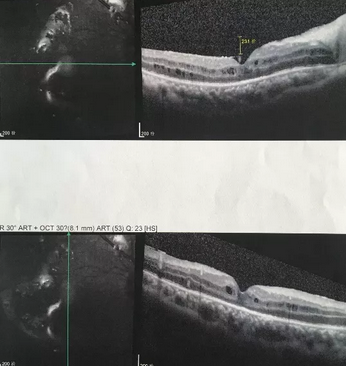

独眼,视网膜全脱离已成窄漏斗状、陈旧性葡萄膜炎、瞳孔后黏连无法散大,且并发白内障使得视网膜周边部细节情况无法看清,左眼已无光感,角膜白斑,瞳孔闭锁,还填充着硅油。右眼既往葡萄膜炎病因不清,一年中发病3、4 次都是用激素医治。左眼多年前是“天那水”溅入后又发生玻璃体出血手术后……令人担心的是这次我们克服重重困难救治全部脱离的视网膜 后,可能会面对长期慢性葡萄膜炎、长期药物医治的继发性高眼压,以及葡萄膜炎的再次复发等,稍有不慎就是不逆性致盲了。

葡萄膜炎等多种眼底病患者跪地感谢深圳易游体育院长赵铁英教授3.png